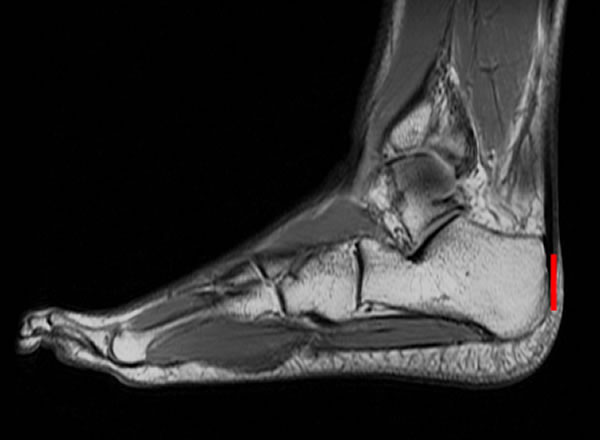

长跑运动员的脚部核磁共振图,跟骨与跟腱紧密连接,测量跟骨的长度(红线)有助于研究者确定长跑能力。

研究者选择了一些长跑运动员来进行测验,运动员在跑步机上以10英里/小时的速度跑10分钟,而研究者则记录下运动员的耗氧率、跟骨与踝骨的图像。结果显示,跟骨与踝骨越是短而平,氧气的使用率越高。对13块来自30000-20000年前的古人类跟骨化石及其同时期的6块尼安德特人跟骨化石的测量结果显示,古人在奔跑时耗费的能量比现代运动员约多6.9%,而尼安德特人则多出11.4%。研究者补充说,虽然解剖学上的特质比起专业训练来讲对奔跑的影响大得多,但是他们在研究过程中还是排除了训练的影响因素以期得到更准确的结果。(蜘蛛网www.eeook.com)